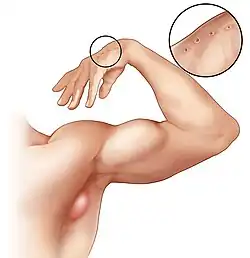

| An enlarged lymph node in the armpit region of a person with cat-scratch disease, and wounds from a cat scratch on the hand. | |

Cat-scratch disease commonly presents as tender, swollen lymph nodes near the site of the inoculating bite or scratch or on the neck, and is usually limited to one side. This condition is referred to as regional lymphadenopathy and occurs 1–3 weeks after inoculation.[5] Lymphadenopathy most commonly occurs in the axilla,[6] arms, neck, or jaw, but may also occur near the groin or around the ear.[4] A vesicle or an erythematous papule may form at the site of initial infection.[4]